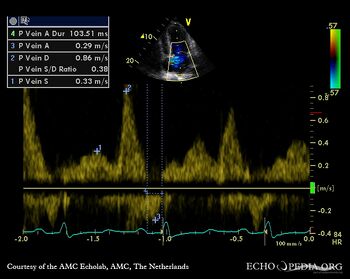

| HCM, diastolic dysfunction

| Courtesy of: AMC Echolab, AMC, The Netherlands

Pulsed-wave doppler signal of pulmonary venous flow